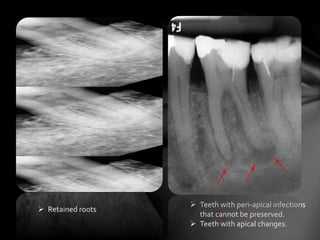

 Retained roots

 Teeth with peri-apical infections

that cannot be preserved.

 Teeth with apical changes.